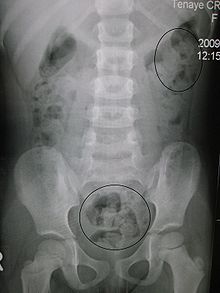

Think about it: Halitosis, hiccups, heartburn, excessive gas, bloating, cramping, nausea, constipation, and diarrhea—all are symptoms of the body trying to either remove an ingested food item, or the effects of that item being digested incompletely. But since your average medical doctor will likely not consider food sensitivities as a factor in your GI disorder, what do you think happens? Yes, he or she will go into the standard medical playbook, consider the symptoms only, and prescribe a treatment based on the severity and duration of those symptoms. Short-term and mild GI symptoms (those on the lower end of the spectrum) will get medicated, while the more severe and chronic cases will receive first a bevy of diagnostic testing (to observe how your physiology is changing—think endoscopy and colonoscopy) and then either medication, surgery or both. No doubt some docs will consider diet to a slight degree in your case management, but rarely will they do so as a serious or long term approach. And that’s where the real fun begins.

Over time this cycle of increasing GI symptoms, to suppression with medications, to even worse GI symptoms, to suppression with more potent medication, to even worse symptoms, is what I believe is the precursor to serious GI diseases—things like Barrett’s esophagus, stomach cancer, acute pancreatitis, cholecystitis, gallstones, Crohn’s disease, and colon cancer. I’m fairly confident that every one of these disorders results from repeatedly eating foods that the body is sensitive to, and ultimately, they act as a form of poison leading to pathophysiology and frank disease.